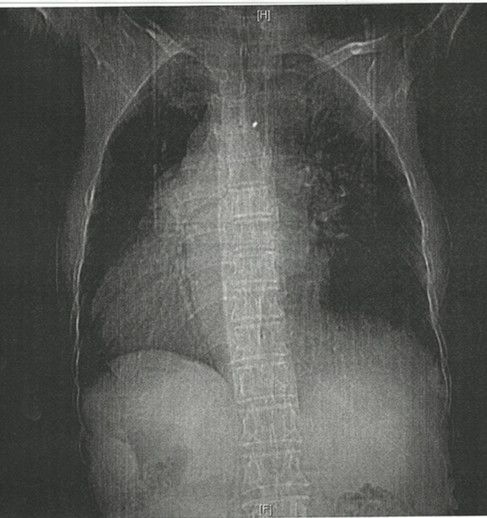

患者的胸导联心电图:V1~V6导联R波逐渐降低,QRS波群振幅逐渐减小,V4~V6导联表现为低电压。由于心脏位于右侧胸腔,V1导联距离心脏最近,故R波最高,QRS波群振幅最高,V1~V6导联逐渐远离心脏,QRS波群振幅逐渐降低。此患者有心脏彩超及胸片证实为右位心。图4为患者胸片表现。

图4. 患者胸片。此患者的胸片、上腹CT+下腹CT证实为全内脏转位。